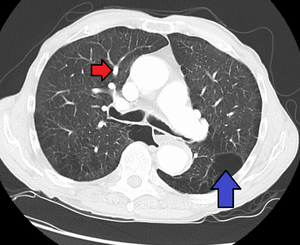

لأن فرط ضغط الدم الرئوي يتكون من خمس أنواع رئيسية -فرط ضغط الدم الرئوي الشرياني، الوريدي، الناتج عن قلة الأكسجين، الناتج عن الامراض التخثرية والانصمامية والناتج عن آليات متنوعة-؛ فانه يتم اجراء سلسلة من الاختبارات للتفريق بينها. يتم عمل اجراءات لاحقة للتأكد من وجود فرط ضغط الدم الرئوي واستثناء الامراض الاخرى, هذه الاجراءات تشمل: اختبار وظائف الرئة؛ تحليل الدم لاستبعاد امراض الايدز والكبد وأمراض المناعة الذاتية؛ مخطط كهربائية القلب؛ قياسات غازات الدم الشرياني؛ صورة أشعة سينية للصدر (متبوعة بصورة طبيقية عالية الوضوح اذا تم الشك بوجود امراض رئوية خِلاليّة)؛ واختبار التهوية/التدفق لاستبعاد فرط ضغط الدم نتيجة الامراض التخثرية والانصمامية المزمنة. لا يتم اخذ خزعة من الرئة الا اذا تم الشك بحدوث فرط ضغط الدم نتيجة لامراض رئوية خلالية؛ أيضاً، هناك تخوّفات ان خزعات الرئة قد تسبب نزيف نتيجة الضغط الرئوي البيني العالي. يتم أيضا قياس درجة التحسن طبيّاً عن طريق "اختبار السير لمدة 6 دقائق", بمعنى آخر، يتم حساب المسافة التي يستطيع ان يقطعها المريض خلال 6 دقائق. كلّما كانت نتائج هذا القياس ثابتة ومتحسنة فهي دليل على وجود فرص أفضل للنجاة.

Long standing pulmonary hypertension[16]